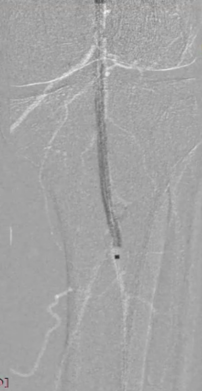

病变类型:严重钙化、长病变

导丝选择:

V-18

Victory™-18,

Asahi Treasure™ 12,

Asahi Astato™ 20,

Asahi Astato™ 30

预扩球囊:

Bantam™ 2x120mm balloon

严重的钙化斑块——定向斑块旋切术

长期严重钙化

长段严重钙化病变因钙化范围广、质地坚硬,常规扩张治疗易出现血管撕裂、夹层等并发症,且管腔开通效果不佳。定向斑块旋切术凭借 “精准切削、靶向清除” 的核心优势,成为这类复杂病变的优选治疗方案,为临床破解长段钙化难题提供了高效路径。